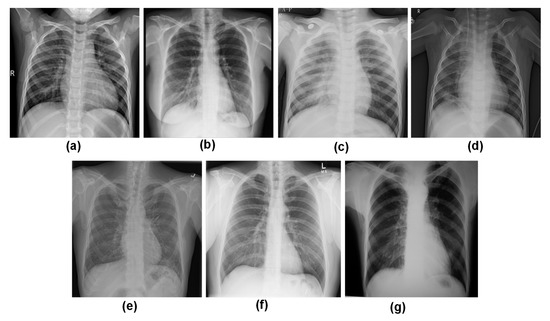

4.7. Grad CAM Visualisation